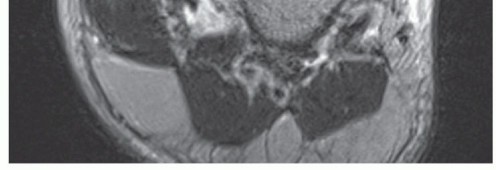

Magnetic resonance (MR) imaging may show an injury to the deltoid ligament (FIG 4), particularly in acute conditions, and it may also reveal pathologic conditions of the posterior tibial tendon.

FIG 4 • Proximal avulsion of the deltoid ligament. AP MR imaging reveals a complete avulsion of the deltoid ligament to the medial malleolus.*